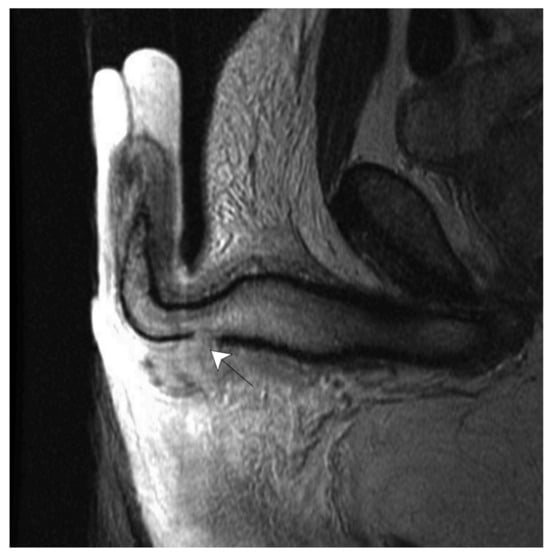

- Choi, M.H.; Kim, B.; Ryu, J.A.; Lee, S.W.; Lee, K.S. MR imaging of acute penile fracture. Radiographics 2000, 20, 1397–1405. [Google Scholar] [CrossRef]

- Guler, I.; Ödev, K.; Kalkan, H.; Simsek, C.; Keskin, S.; Kilinç, M. The value of magnetic resonance imaging in the diagnosis of penile fracture. Int. Braz. J. Urol. 2015, 41, 325–328. [Google Scholar] [CrossRef] [PubMed]

- Saglam, E.; Tarhan, F.; Hamarat, M.B.; Can, U.; Coskun, A.; Camur, E. Efficacy of magnetic resonance imaging for diagnosis of penile fracture: A controlled study. Investig. Clin. Urol. 2017, 58, 255–260. [Google Scholar] [CrossRef]

- Sokolakis, I.; Schubert, T.; Oelschlaeger, M.; Krebs, M.; Gschwend, J.E.; Holzapfel, K.; Kübler, H.; Gakis, G.; Hatzichristodoulou, G. The role of magnetic resonance imaging in the diagnosis of penile fracture in real-life emergency settings: Comparative analysis with intraoperative findings. J. Urol. 2019, 202, 552–557. [Google Scholar] [CrossRef]

- Spiesecke, P.; Mang, J.; Fischer, T.; Hamm, B.; Lerchbaumer, M.H. Diagnostic performance of MRI and US in suspicion of penile fracture. Transl. Androl. Urol. 2022, 11, 377–385. [Google Scholar] [CrossRef] [PubMed]